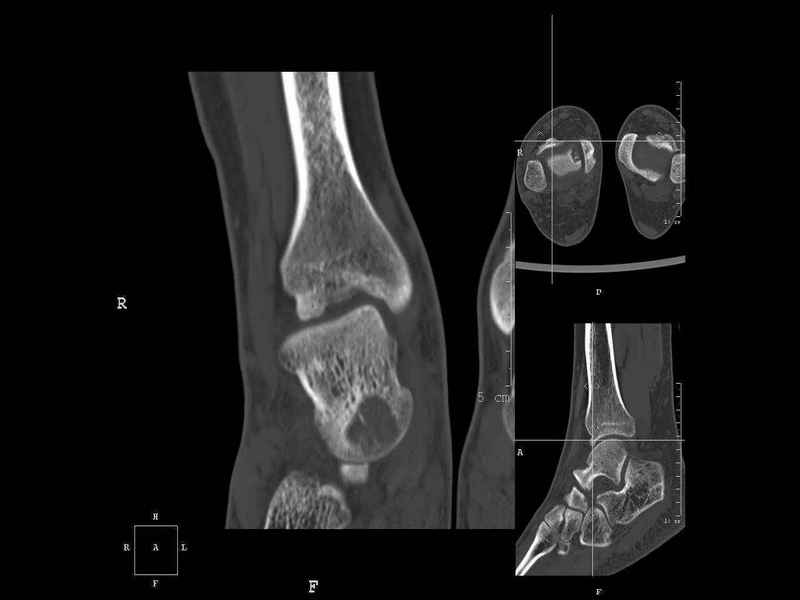

[Ortho] Рассекающий остеходрит + киста шейки тарана

Уважаемые коллеги, обратился за помощью пациент, мужчина, 25 лет. С жалобами на болевой

синдром в области голеностопного сустава и среднем отделе стопы. Травму отрицает. Со слов,

болевой синдром в течении 1 года. Последние 1-1.5 мес периодически вынужден пользоваться

костылями. После ограничения нагрузки боли уменьшаются. Соматически здоров. До появления

болей активно занимался рукопашным боем.

На СКТ картина рассекающего остеохондрита блока

таранной кости, киста шейки таранной кости с признаками импрессии суставной поверхности. А

также - разрастания переднего края б\берцовой кости сопровождающиеся клиникой импиджмент

синдрома.